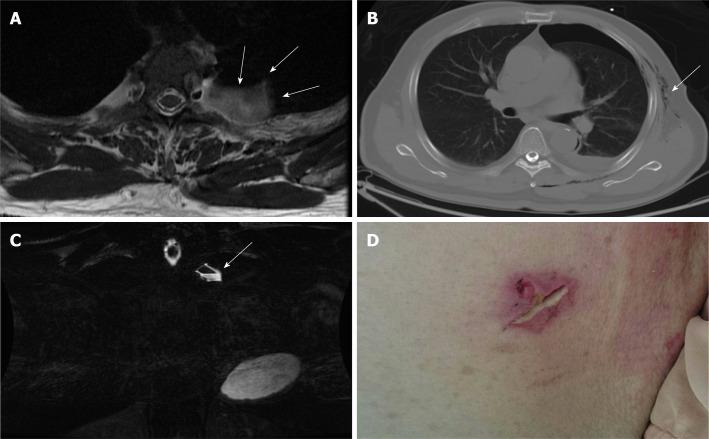

A 66-year-old man who received thoracoscopic resection to remove an intrathoracic, posterior mediastinal, dumbbell-shaped, pathology-proven neurogenic tumor. The patient then reported experiencing progressively severe headaches, especially when in an upright position. A brain computed tomography scan at a local hospital disclosed extensive pneumocephalus. Revision surgery for resection of the pseudomeningocele and repair of the cerebrospinal fluid leakage was thus arranged for the patient. During the operation, we traced the cerebrospinal fluid leakage and found that it might have derived from incomplete endoscopic clipping around the tumor stump near the dural sac at the T3 level. After that, we wrapped and sealed all the possible origins of the leakage with autologous fat, tissue glue, gelfoam, and duraseal layer by layer. The patient recovered well, and the computed tomography images showed resolution of the pneumocephalus.

一名66岁男性接受胸腔镜切除术以切除一枚位于胸腔内、后纵隔的哑铃形、病理证实的神经源性肿瘤。患者随后报告头痛逐渐加重,尤其是在直立位时。当地医院的脑部计算机断层扫描显示广泛气颅。因此为患者安排了修复假性脑膜膨出和修复脑脊液漏的翻修手术。手术中,我们追踪脑脊液漏,发现其可能源于T3水平硬脊膜囊附近肿瘤残端周围内镜夹闭不完全。之后,我们用自体脂肪、组织胶、明胶海绵和硬脑膜封闭剂逐层包裹并密封所有可能的漏出部位。患者恢复良好,计算机断层扫描图像显示气颅消失。